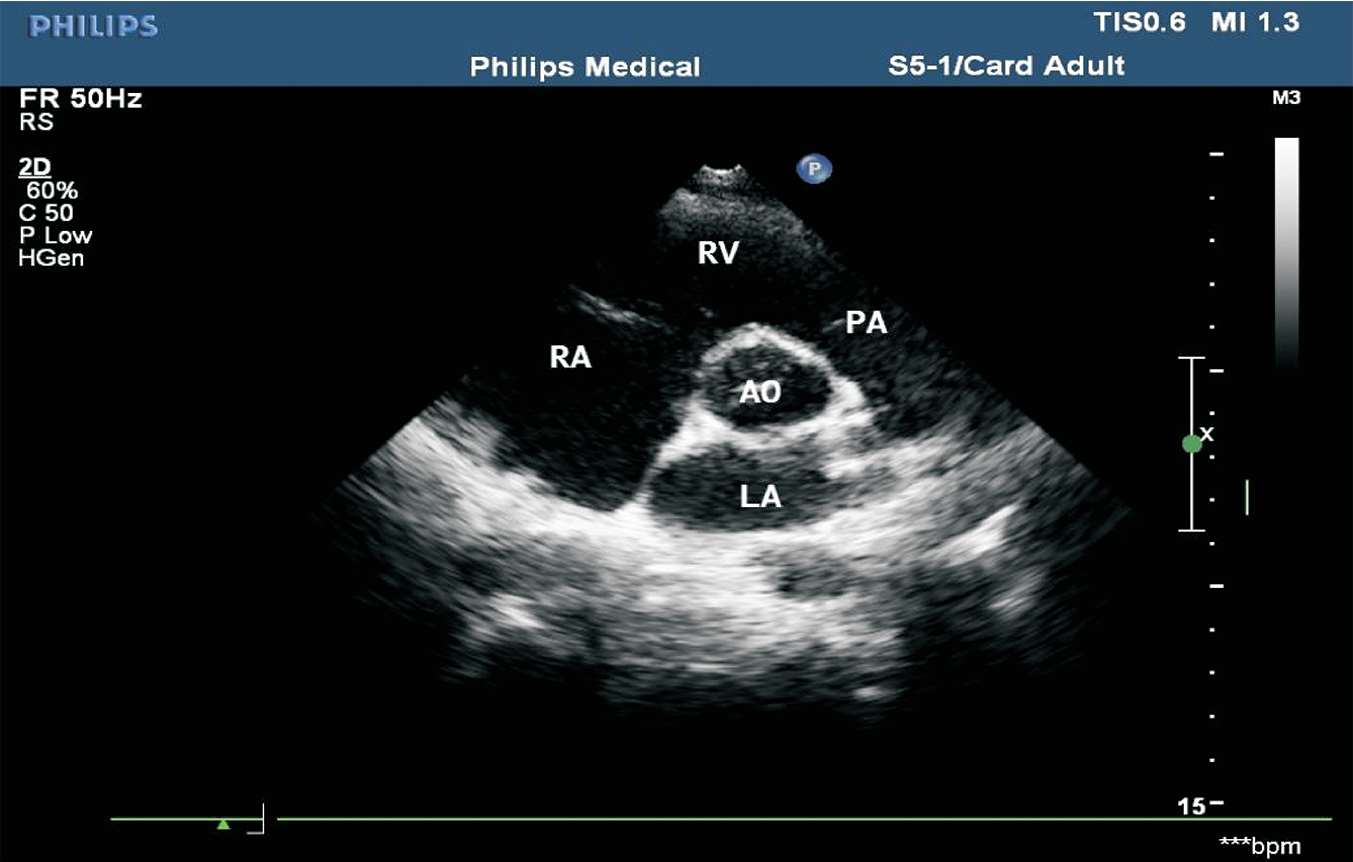

患者取左侧卧位或平卧位,探头置于胸骨左缘第2~3 肋间,声束垂直于胸骨旁左心室长轴切面。在此切面可观察主动脉瓣的形态、厚度、回声强度及开闭状态,右心室流出道与肺动脉干有无增宽、狭窄,降主动脉与肺动脉之间有无异常通道,肺动脉瓣的形态及活动(见图1-27)。正常主动脉瓣呈三瓣叶,收缩期开放为“▽”形,舒张期关闭为“Y”形(见图1-28)。

图1-27 心底大动脉短轴切面(RA:右心房;RV:右心室;PA:肺动脉;AO:主动脉;LA:左心房)